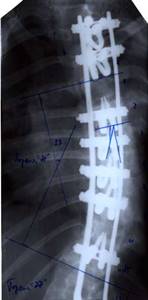

| Больной Т-ов, 16 лет Сколиоз IV степени. До операции |

|

| Внешний вид больного на 10 день после операции |